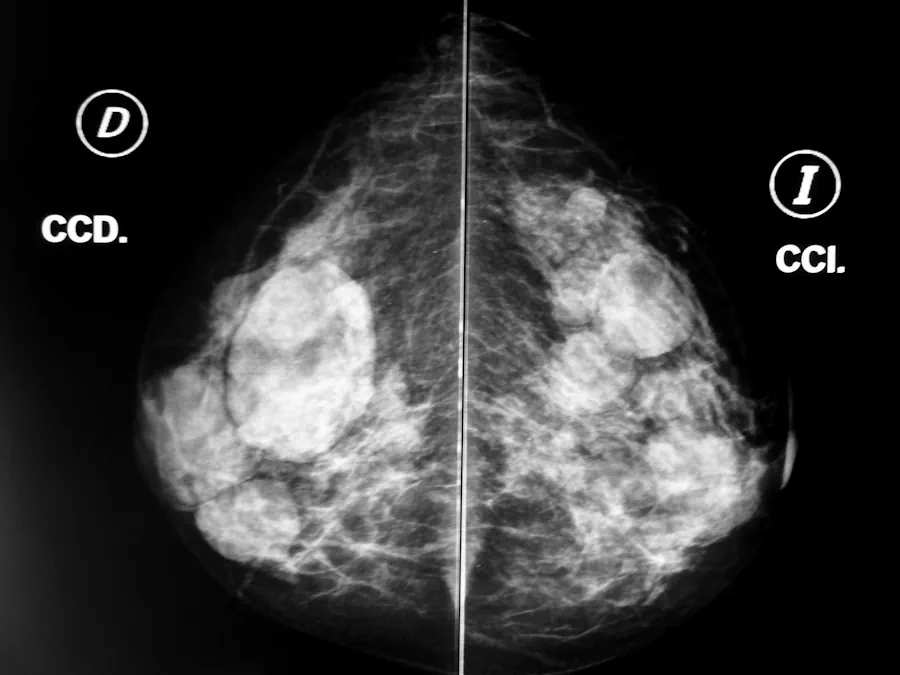

La detección precoz del cáncer de mama en Andalucía se ha visto sacudida por una crisis sanitaria: al menos 2.000 mujeres esperan resultados no comunicados correctamente, la consejera de Salud dimitió y la Junta ha lanzado un plan de choque con política de recursos y modificaciones de protocolo. En este artículo desgranamos el origen, las consecuencias y las reacciones de esta crisis.

El descontrol estalló al conocerse que muchas mujeres que participaron en el programa de cribado del cáncer de mama no fueron informadas cuando los resultados de sus mamografías eran “no concluyentes”, lo que dejó a cientos de ellas en un limbo diagnóstico. La Junta, en un principio, limitó el problema al Hospital Virgen del Rocío en Sevilla, alegando que allí se concentraban el 90 % de los casos problemáticos. Manuel Gavira ha anunciado que se pedirá una comisión de investigación en el Parlamento de Andalucía para esclarecer que ha pasado.

Con el avance de las investigaciones y denuncias, la crisis se amplió: se reveló que el sistema andaluz depende de un protocolo de 2011 que no obliga a informar a las mujeres cuando los resultados no son concluyentes, algo que entidades críticas consideran un “protocolo de la vergüenza”. Además, este fallo no parece ser reciente: las primeras denuncias señalaban que las irregularidades eran conocidas internamente desde hace hasta año y medio sin que se hubieran tomado medidas.